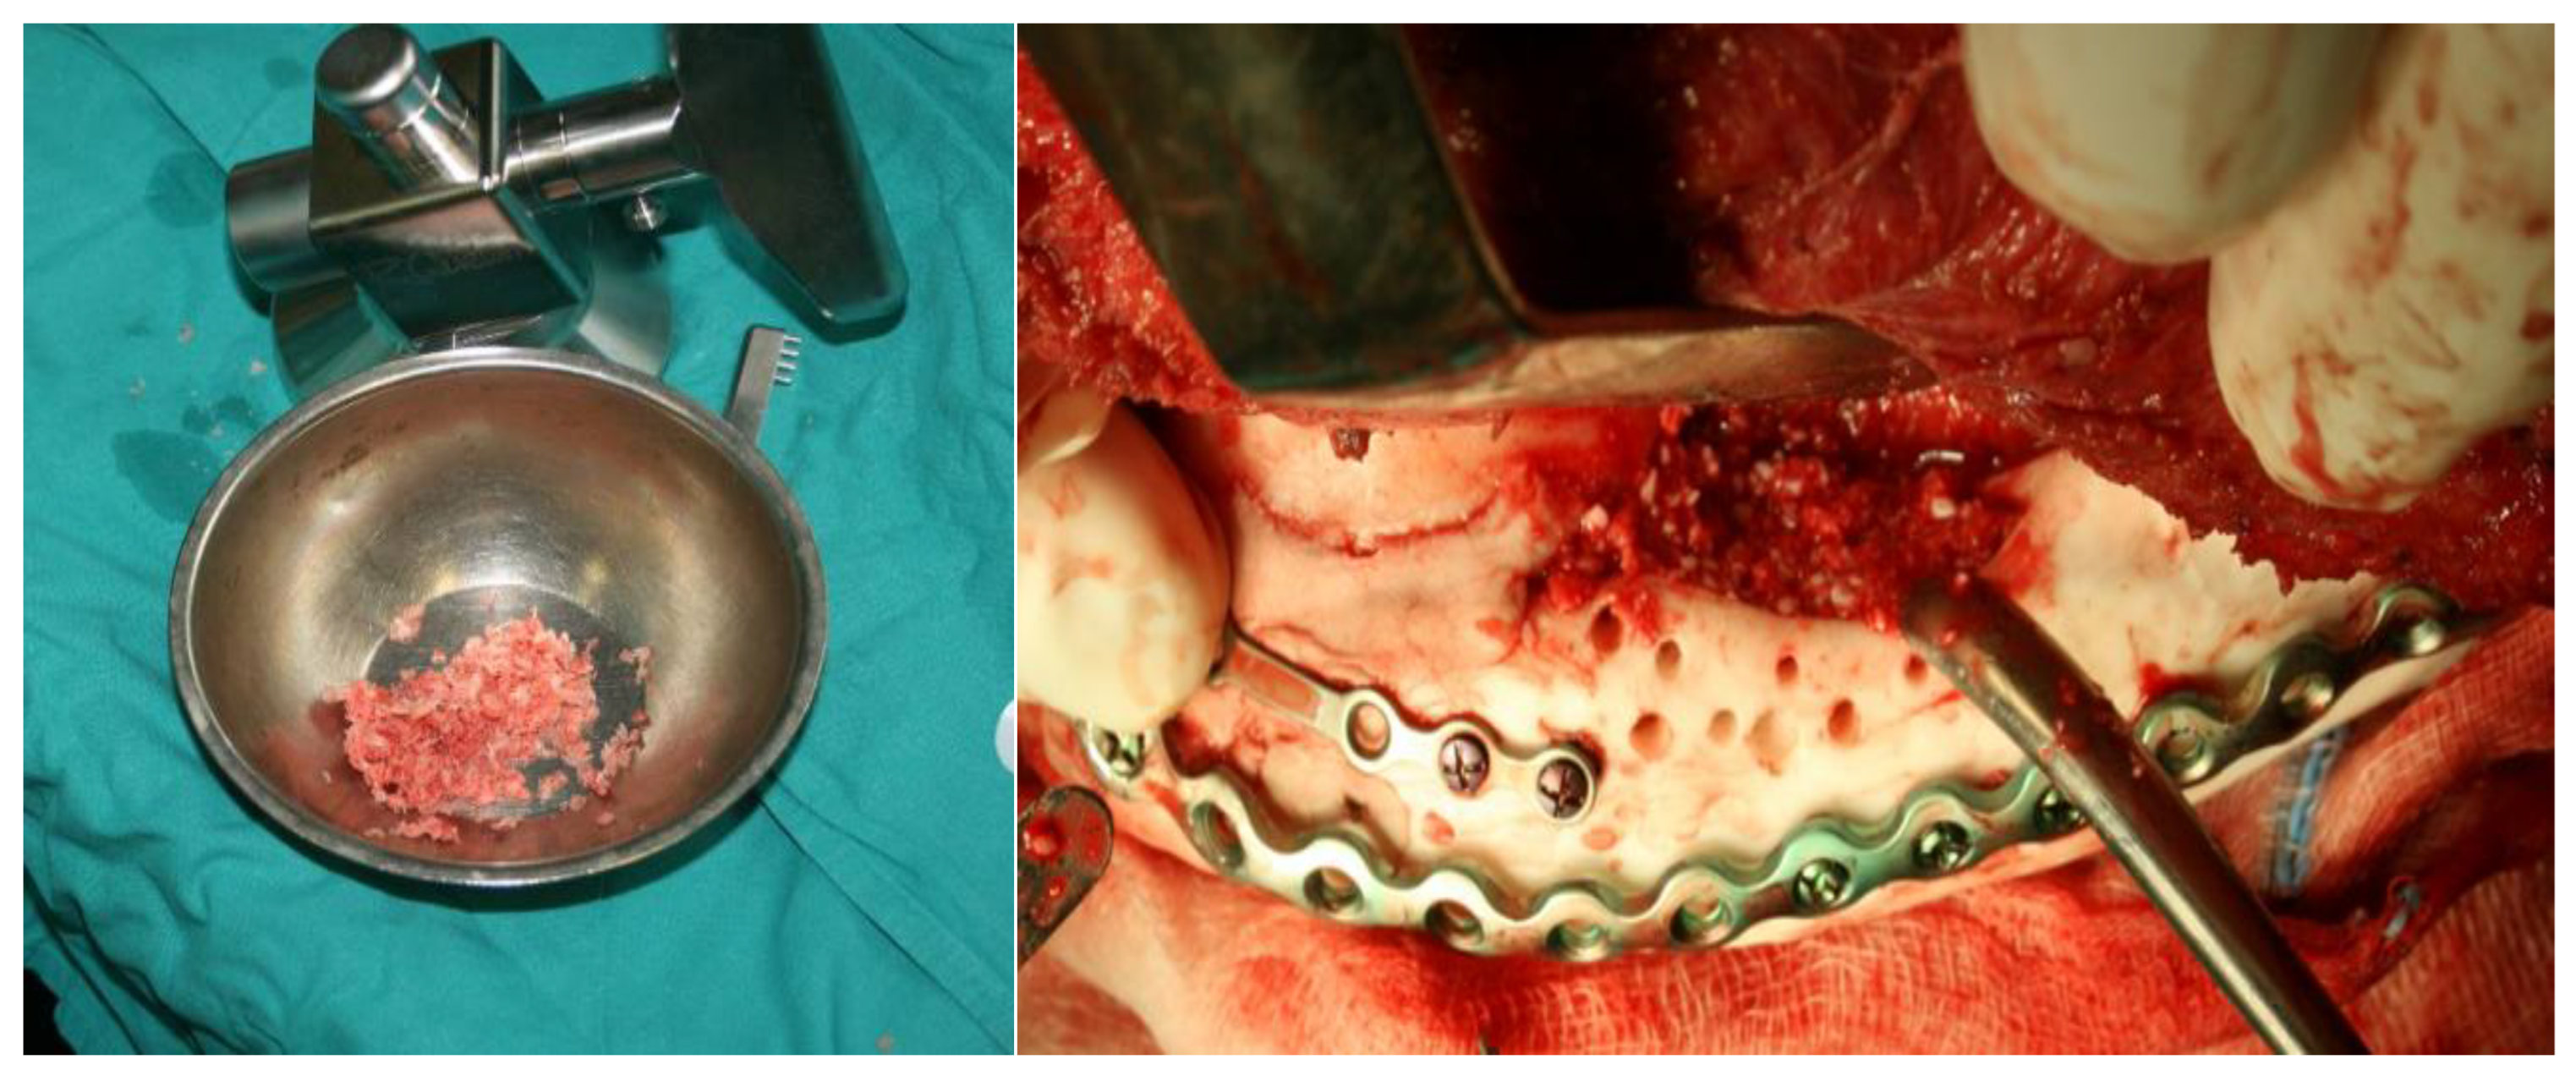

- phase 1: Mixing two-component material, liquid and powder

- phase 2: Hardening of the material

- phase 3: 3D printed mold

- phase 4: Cutting the model into the final shape of the implant

4. Discussion